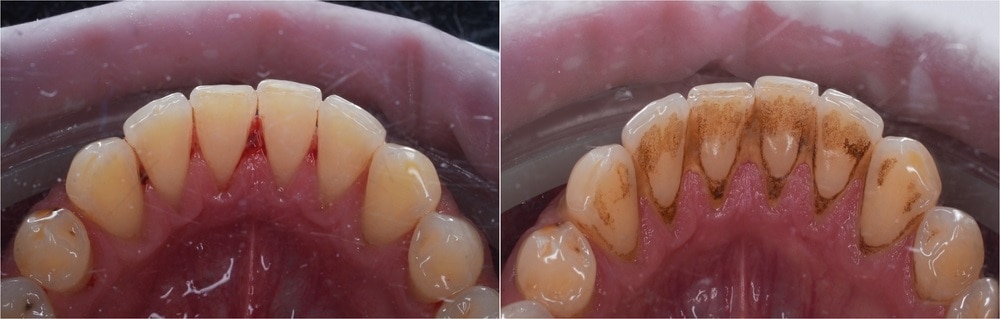

Sự khác biệt của răng và nướu sau khi cạo vôi răng

• Cao răng thường: Cao răng thường hình thành phía trên đường viền nướu, có màu trắng đục hoặc vàng nhạt. Đối với những người thường xuyên hút thuốc lá sẽ có màu sẫm hơn. Cao răng thường nếu kéo dài sẽ gây viêm nướu, chảy máu chân răng,...

• Cao răng huyết thanh: Cao răng thường nếu không điều trị kịp thời, gây chảy máu nướu, máu ngấm vào mảng bám chuyển thành màu nâu đỏ gọi là cao răng huyết thanh. Cao răng huyết thanh xuất hiện trong khe hở (kẽ) giữa răng và đường viền nướu. Cao răng này thường có màu nâu hoặc răng đen và chứa nhiều vi khuẩn hơn, gây viêm nướu và đẩy nhanh tốc độ nhiễm trùng chân răng.